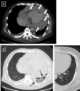

Infectious pericarditis

Pericarditis is inflammation of the pericardium (the fibrous sac surrounding the heart). Symptoms typically include sudden onset of sharp chest pain, which may also be felt in the shoulders, neck, or back. [Source: Wikipedia ]